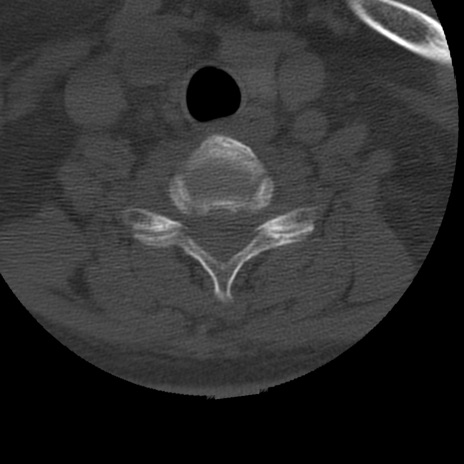

症例50 頚椎CT(横断像)

異常所見と診断は?

頚椎CT